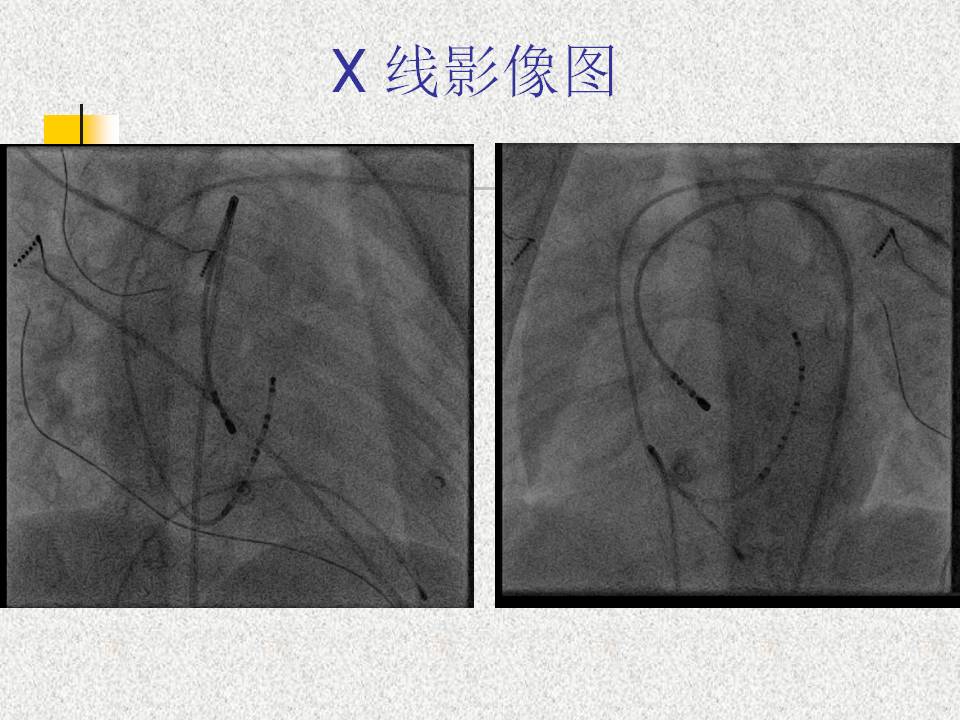

无冠窦内消融前间隔旁道1例